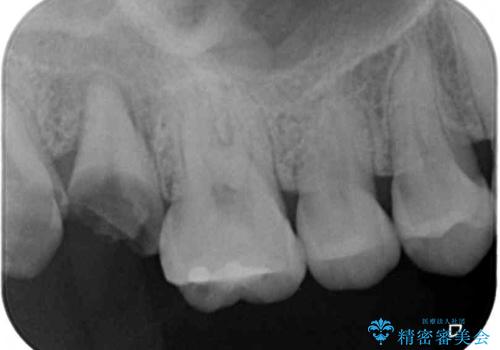

神経組織の失活している歯や歯根だけが残っている歯などがあり、全体的に歯石も多く付着している状態でした。

まずは歯石除去とブラッシング方法などの衛生指導を徹底的に行って口腔内環境を改善し、汚れの溜まりやすくなっている親知らずは全て抜去することとしました。

その後、歯根だけとなっている歯はインプラントに、神経組織の失活している歯は根管治療を行い、いずれもオールセラミッククラウンにて補綴治療を行うこととしました。